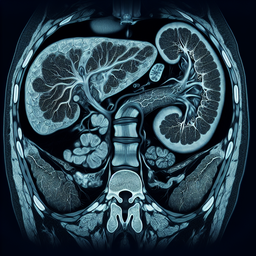

МРТ (магнітно-резонансна томографія) підшлункової залози – це неінвазивний метод діагностики, що використовує магнітне поле і радіохвилі для створення докладних зображень цього органа.

- **Висока якість зображень:** дозволяє чітко бачити структуру підшлункової залози та навколишніх тканин.

- **Контрастність м'яких тканин:** забезпечує кращу візуалізацію пухлин, запальних процесів чи інших патологій.